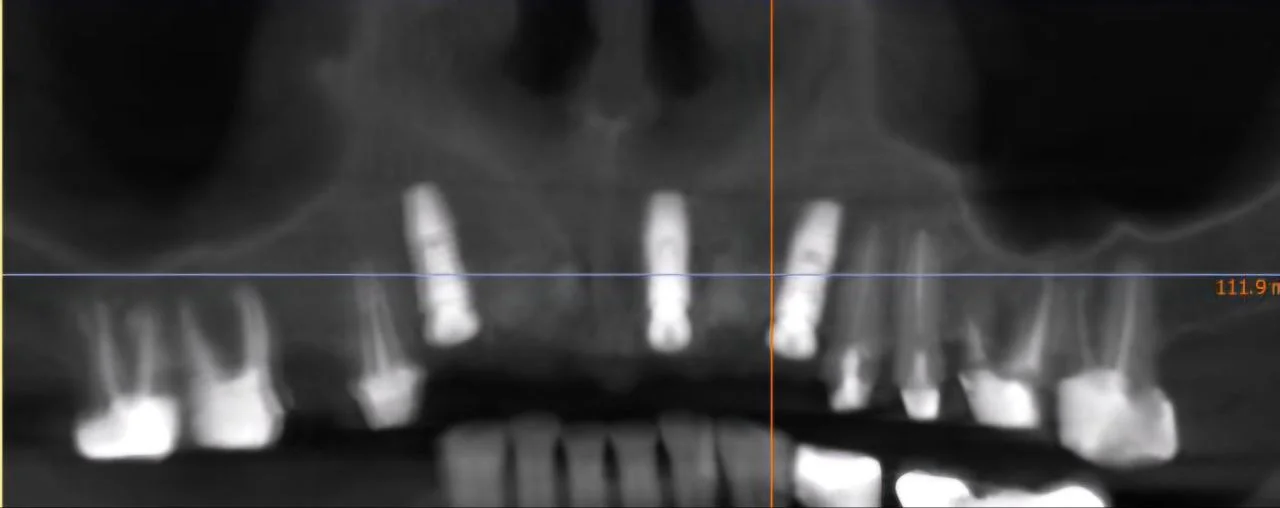

Видалення 4-х зубів, імплантація 4 імплантів Штрауман. Закритий синус-ліфтинг, кісткова пластика.

Екстракція зубів за пародонтологічними показами, все на 6-х імпл верхня та нижня щелепа, вже запротезований постійно 2 роки.

Видалення 4-х центральних різців, одномомента імплантація в ділянки 13, 21, 23, Кісткова пластика, тимчасові коронки.